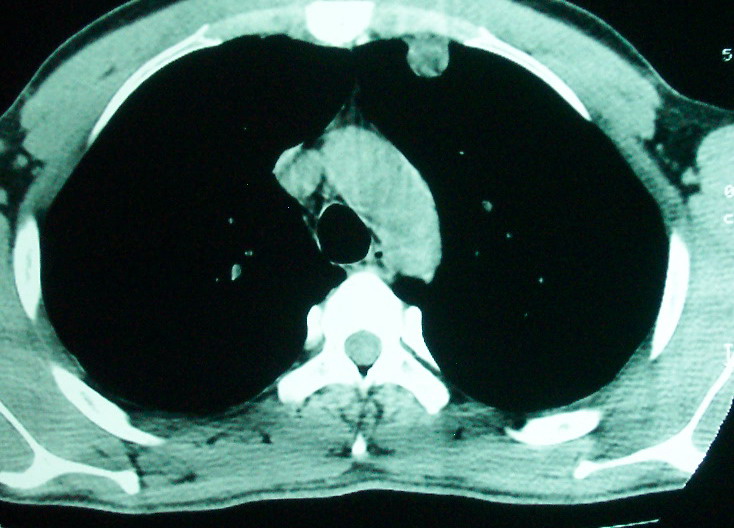

左下肺病灶除了明显的厚壁空洞 气液平外,明显见壁结节,另两肺多发小结节,综合考虑:左下肺周围性肺癌伴肺内转移.

鳞癌肺肺转移:厚壁空洞,洞壁厚薄不均,内似有壁结节,肺脓肿临床有无提示,血像如何?病灶周围很干净,没有明显渗出,很勉强?

我看是不是可以两元化来解释,左肺下叶还是肺脓疡,而其余病灶考虑肺癌伴肺内转移,我看右肺上叶尖段病灶可见明显毛刺改变为原发病灶.

1、左下肺鳞癌伴两肺及纵隔淋巴结转移;

2、两上肺支扩伴慢性炎症。